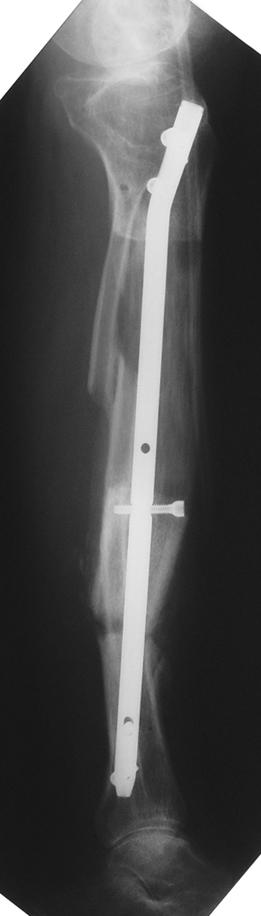

The duration of external fixation (external fixation index) depends on the amount of distraction required, and the extremity is prone to complications during this period. After the distraction phase is completed, the external fixator remains in place during the consolidation phase, which lasts twice as long as the distraction phase; but this period is hardly tolerated. If the external fixator is removed before sufficient consolidation is achieved, fractures, deformity and shortness will be the result. In our department, ‘lenghthening over nail’ method is used in order to decrease the external fixation index and increase patient comfort and activity level. In this method, the intramedullary nail is statically locked after the completion of the distraction phase, and external fixator is removed. The extremity is stabilized by the intramedullary nail during consolidation phase. In this way, complications due to long external fixation index or early removal of the external fixator are avoided.